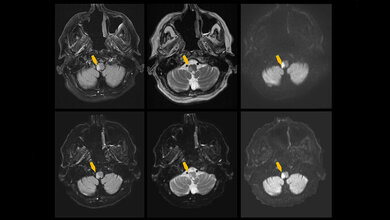

Entscheidend sei laut Studienleiterin Prof. Dr. Catherine Sweeney-Reed auch der Zeitpunkt der Synchronisation: „Dabei ist entscheidend, ob der Zeitpunkt der Erkennung eines Bewegungsversuchs im Gehirn mit dem Beginn der Muskelstimulation synchronisiert wird. Wenn beides nahezu gleichzeitig erfolgt, wird die Wiederherstellung der Verbindung zwischen Hirnsignalen und Bewegungen unterstützt.“ Elektrophysiologische Messungen lieferten ebenfalls Hinweise darauf, dass die Verbindung zwischen Hirnaktivität und Muskelbewegung wiederhergestellt wird.